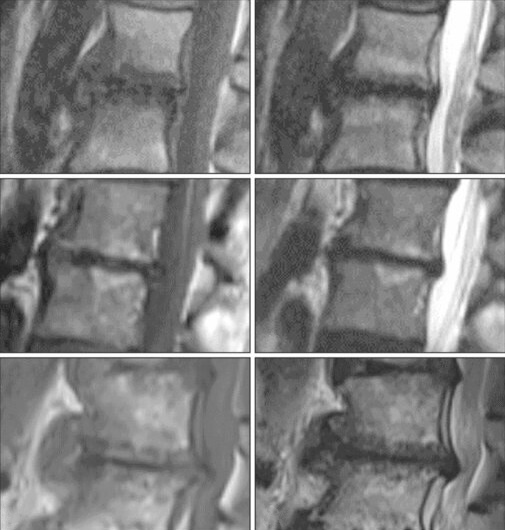

Séquences sagittale T1, sagittale et coronale T2 STIR, ainsi que 3D T2.

Discopathie dégénérative prédominant en avec remaniements de type Modic .

Modic I = inflammatoire « œdémateux », II = involution graisseuse, III = fibrose

Modic I = inflammatoire « œdémateux », II = involution graisseuse, III = fibrose